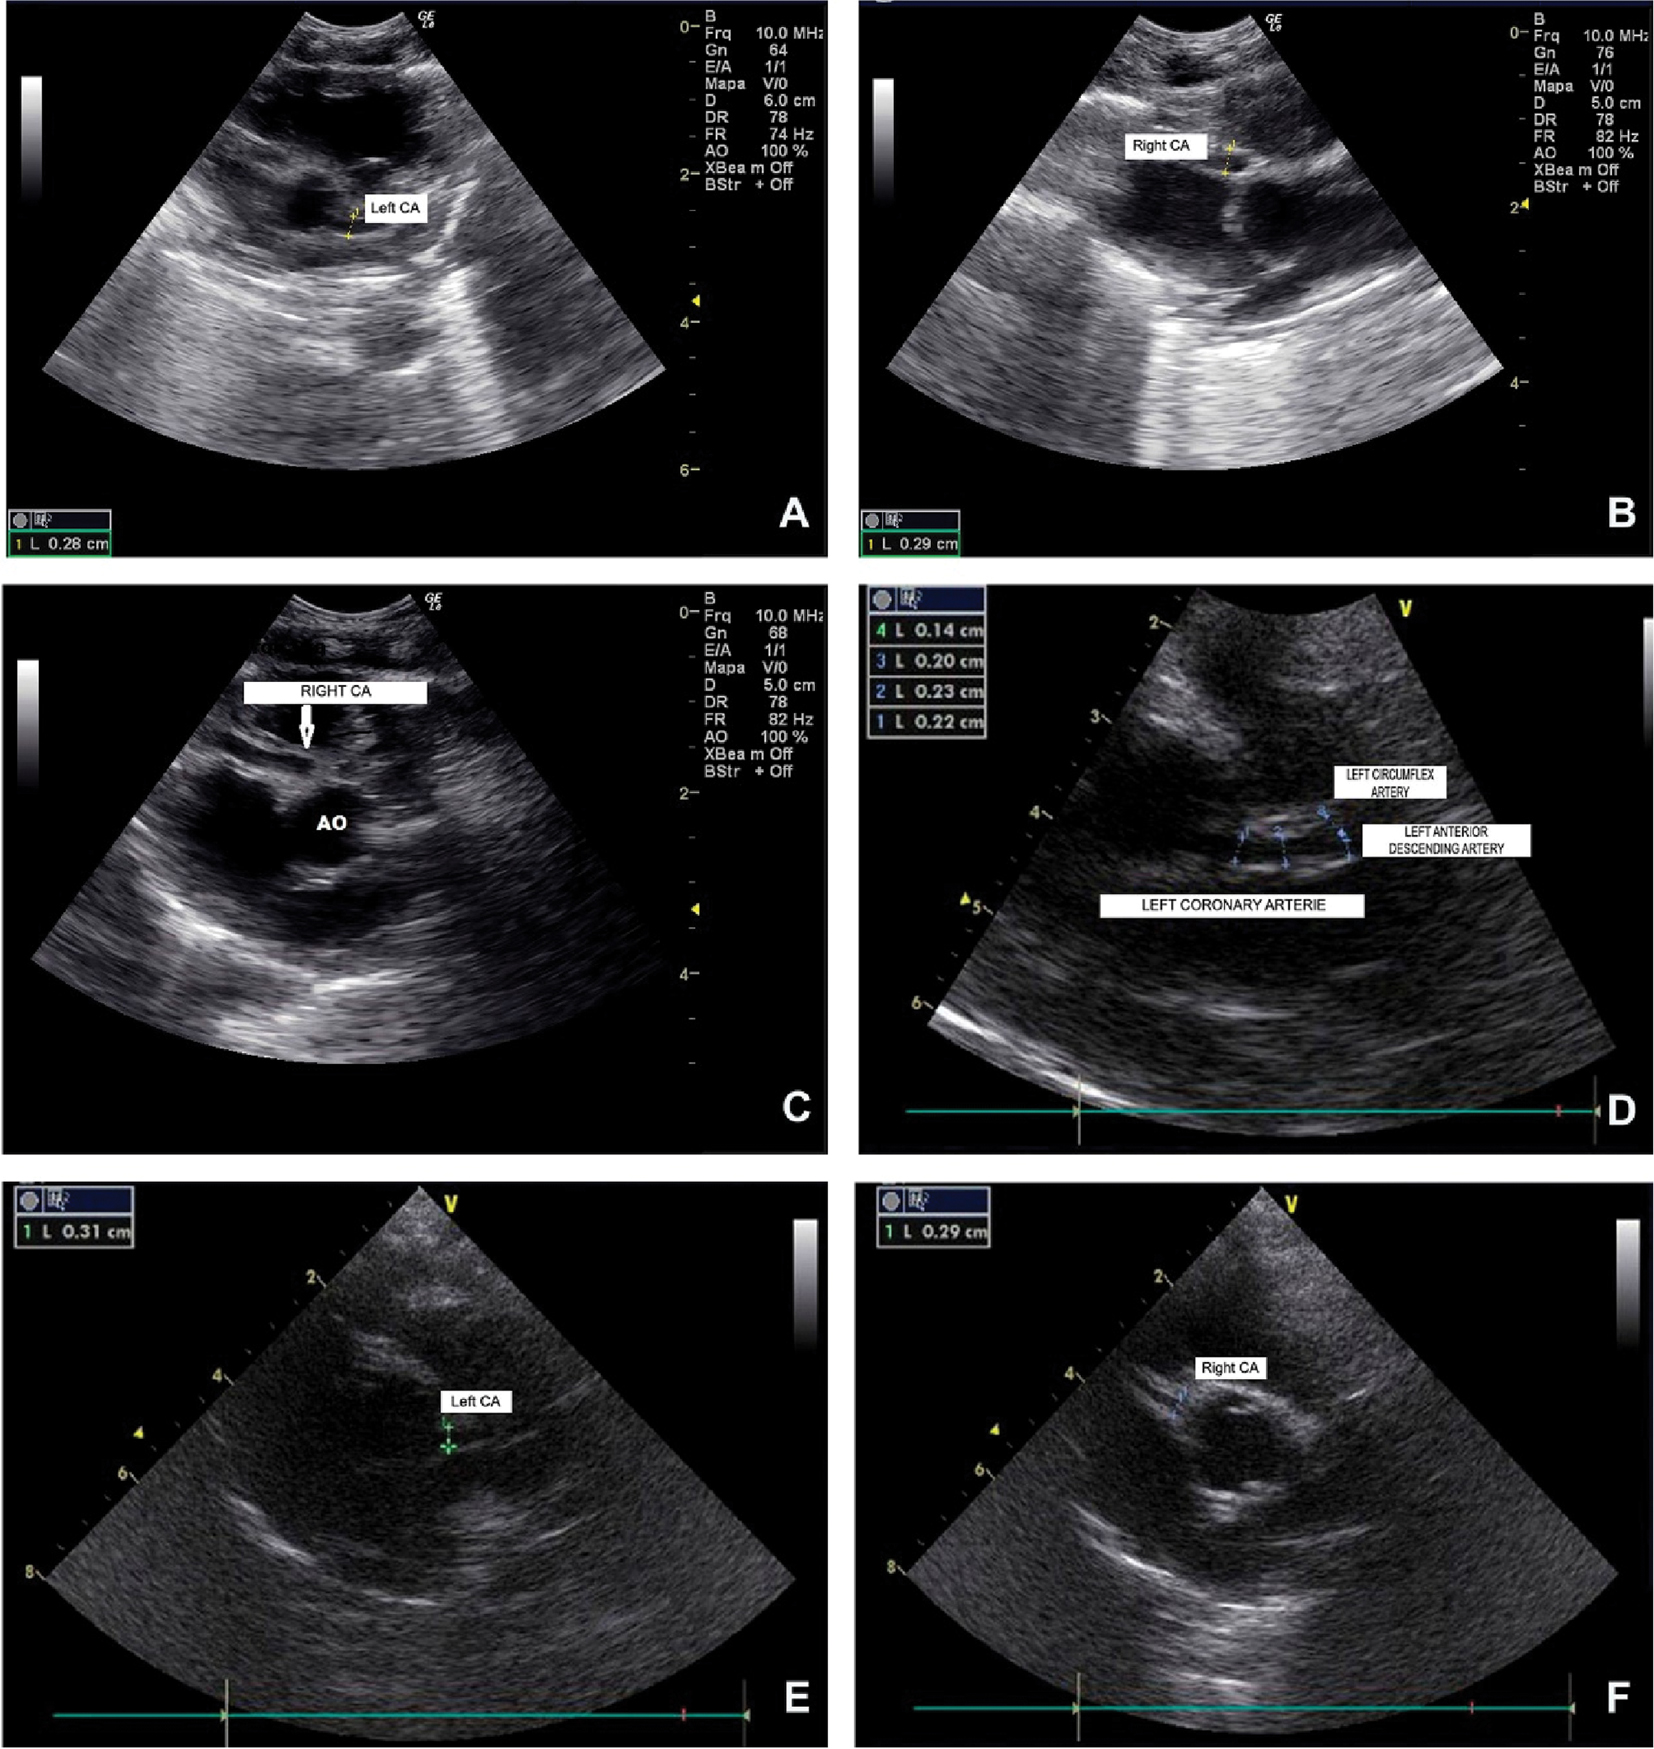

On the 5th day a systolic murmur was detected, and an echocardiogram was performed, which revealed dilatation of both coronary arteries, as shown in Figure 1A (left CA 2.8 mm or 0.28 cm – Z score 5.07) and Figure 1B (right CA: 2.9 mm or 0.29 cm – Z score 6.09). The diagnosis of KD was considered. However, there were no other symptoms and the patient remained afebrile, therefore, the existence of a congenital coronary artery fistula [5] was considered as a possible diagnosis. It was only on the 6th day that other classic signs of KD progressively started to appear, such as a polymorphous rash (Figure 2), conjunctival injection, edema and erythema of the lips and strawberry tongue.

Consecutive echocardiograms of the newborn, performed on the 5th (1A and 1B) and the 10th day postpartum (1C), and subsequently on the 7th (1D) and the 10th month of life (1E and 1F), showing the appearance of bilateral coronary artery aneurysms and their eventual final normalization.

A repeated echocardiogram, at 1 month, disclosed unchanged CA parameters. A new echocardiogram performed at 7 months showed decreasing diameters of the coronary arteries [right CA: 0.31 cm – Z score 5.04 (image not shown); left CA: 0.21 cm – Z score 3.83], and the appearance of a small aneurysm on the left anterior descending coronary artery (Figure 1D). On this same occasion, auditory evoked potentials and Doppler ultrasonography of the abdominal arteries were reported normal. A control echocardiogram was performed at 10 months and displayed left CA with a diameter of 0.31 cm (Z score 4.2) (Figure 1E), and right CA with 0.29 cm (Z score 4.15) (Figure 1F). A follow-up exam and echocardiogram were performed at 14 months, which revealed normalization of the coronary arteries. Furthermore, the child was in good clinical condition, with normal height and weight for age, and normal cognitive and motor development.